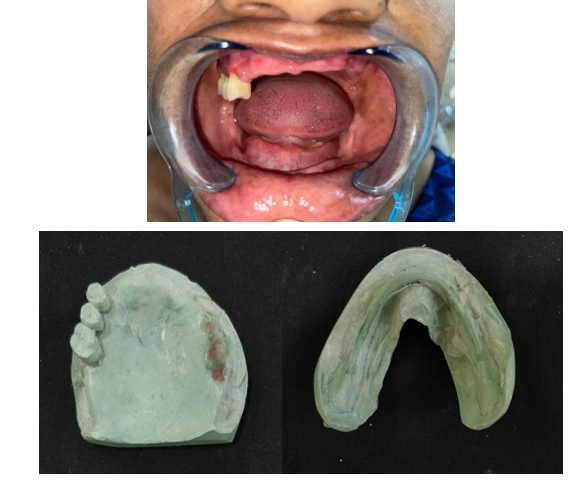

Primary impressions of maxillary and mandibular arches were made using impression material (Y Dents, MDM Corporation, Delhi). Custom trays were made using autopolymerizing acrylic resin. Border molding was done using low fusing impression compound (DPI Pinnacle, The Bombay Burmah Trading Corporation Limited, Mumbai, India) and wash impression was made with medium body addition silicone impression material (Aquasil, Dentsply). Jaw relations were recorded. For the try-in appointment waxed denture was first tried for occlusion and esthetics. At the same appointment, cheek plumpers were made in wax and were attached to the upper waxed-up denture. Then it was evaluated to give the patient a fuller appearance. A dramatic change in the appearance with and without wax-up cheek plumper was observed and it was immediately accepted by the patient. The waxed plumper was separated from the waxed-up denture. After that flasking and dewaxing procedures were completed separately for the final prosthesis and cheek plumpers. The mold space was packed with heat-polymerizing acrylic material (DPI, Mumbai, India) and curing procedures were performed according to the manufacturer’s instructions. After deflasking, the cured final prosthesis and plumpers were retrieved. Trimming, finishing, and polishing procedures were performed. Then a pair of commercially available magnets (cobaltsamarium, Ambika Corporation, New Delhi, India), 5 mm in diameter and 2 mm in thickness was employed to retain the cheek plumper with final prosthesis. Provision for placement of magnets in the flange of the final prosthesis and in the cheek plumper was made and positioned with the help of autopolymerizing resin. Complete polymerization was ensured by placing in a pressure pot and finishing and polishing was then carried out. The attachment of plumper to the prosthesis was first checked outside the patient’s mouth. The prosthesis along with the plumper was then checked in the patient’s mouth. for comfort, function and esthetics . The patient was educated about the positioning of the plumper to the prosthesis. The patient’s demands were fulfilled.  She was called form follow up to evaluate any soreness or looseness of dentures.

In an edentulous patient, this can be achieved by correct contours and extensions of denture flange. Sunken cheeks may require additional support to lift the cheek to an adequate level. Cheek plumper prosthesis can be an amazing solution for such patients. Cheek plumper can be of detachable and non-detachable types. In detachable cheek plumper, the plumper is made separately and attached to the dentures with various attachments like magnets, die pin, snap button, and customized attachments.7

In this case magnets were used, magnets have the benefit of being small, facilitating automatic reseating because of their magnetic forces, and being easy to remove and clean, simplicity of the clinical and laboratory procedures, and constant retentive force with the consecutive number of insertion-removal cycles.9